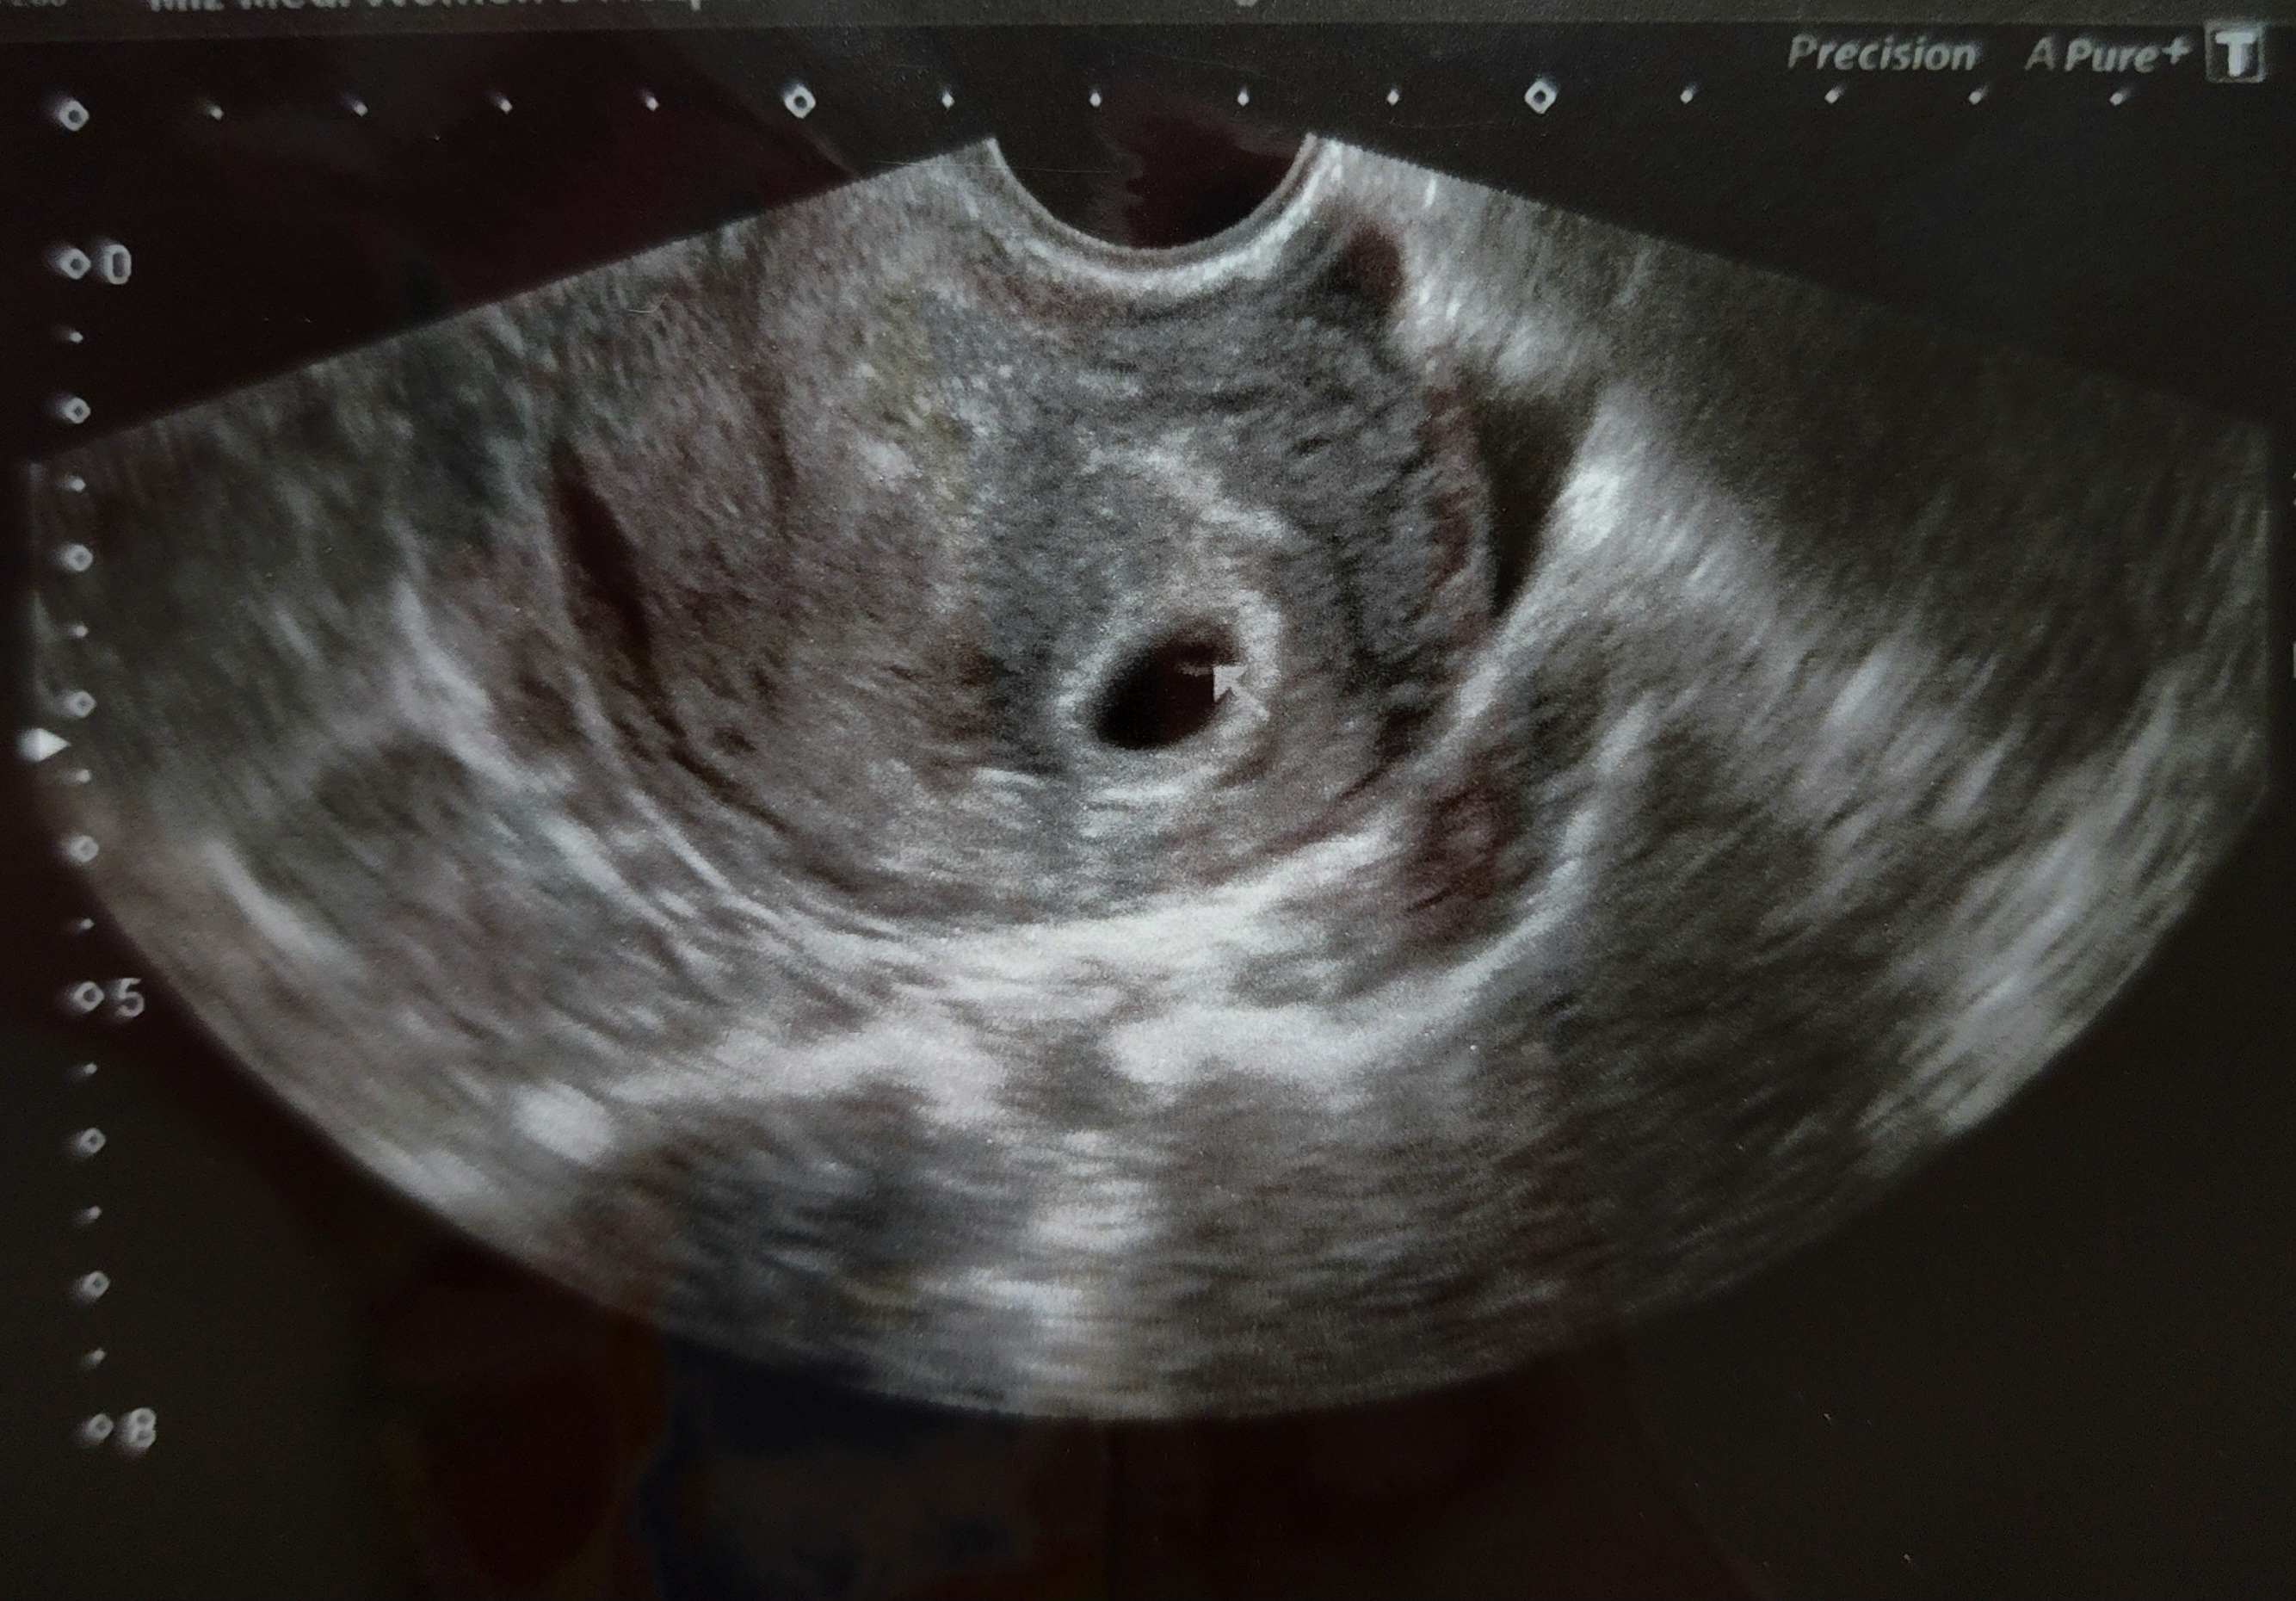

잠시 후, 화면에 선명한 동그란 아기집이 나타났다.

아기집 지름은 약 1cm, 그 안에 희미하지만 난황까지 확인됐다.

선생님은 아기집의 모양, 위치, 크기 모두 좋다고 하셨다.